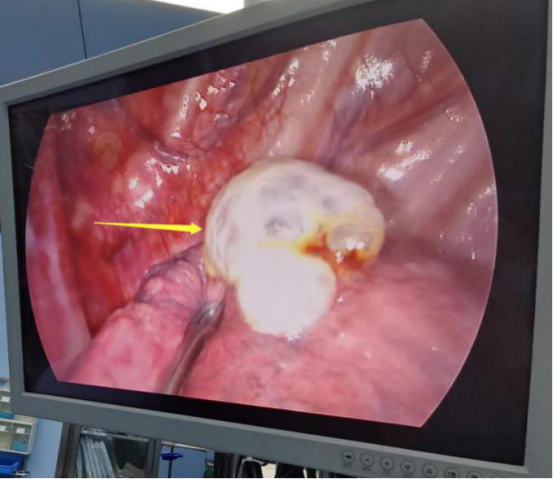

手術(shù)過程中。

患者肺大泡明顯,術(shù)后切口較小。